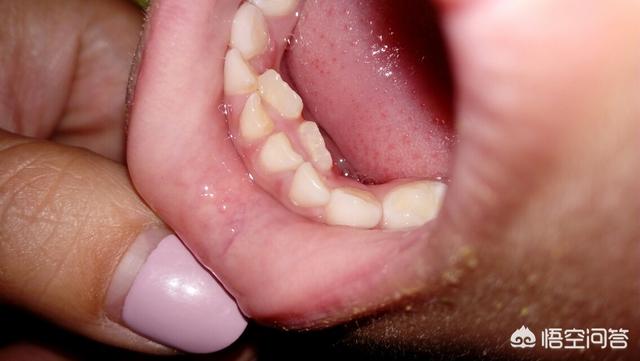

我家老大最近也是这种情况。

这个情况还是被当护士的妹妹发现的,我们都没有注意,当天带去看牙医,牙医说“必须把外面两颗牙给拔了”

抜完以后是这样的。